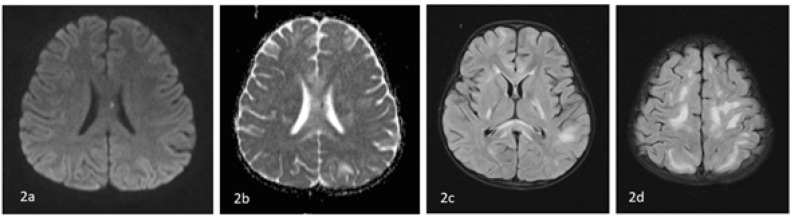

Results: There were 10 cases in the age range of 1-15 years. All the cases had elevated COVID-19 antibodies with history of contact 2-3 weeks prior except one who was positive for COVID-19 infection. Two cases presented with acute ascending paralysis suggestive of Guillain-Barre syndrome. Four cases presented with features of encephalopathy with clinical presentation fulfilling the criteria of Multisystem inflammatory syndrome in children. One case presented with fever and focal seizures with MRI showing sagittal sinus thrombosis, and one presented with fever and altered sensorium with MRI showing leukoencephalopathy. One child had cerebral mucormycosis without any evidence of immunosuppression. There was one child with features of encephalopathy with active COVID-19 infection.